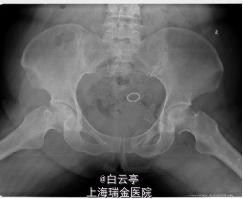

主诉:左侧髋关节疼痛2月。 现病史:患者近2月长时间步行后感左侧髋关节疼痛,疼痛位于腹股沟中点,休息后可有缓解。患者既往sle,长期服用强的松5mg,qd。

体检: 4字试验阳性。双侧髋关节内收外展正常,内外旋活动度可,稍感不适。 辅检: x片提示左侧股骨头低密度病灶。

诊断:双侧股骨头坏死。 治疗:左侧:钻孔减压+对侧髂骨移植+钽棒植入。右侧: 钻孔减压